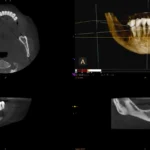

- nowoczesny sprzęt: wyposażenie gabinetu stomatologicznego to jedna z wizytówek miejsca pracy stomatologa, wykorzystanie innowacyjnego sprzętu umożliwia precyzyjne wykonywanie zabiegów,